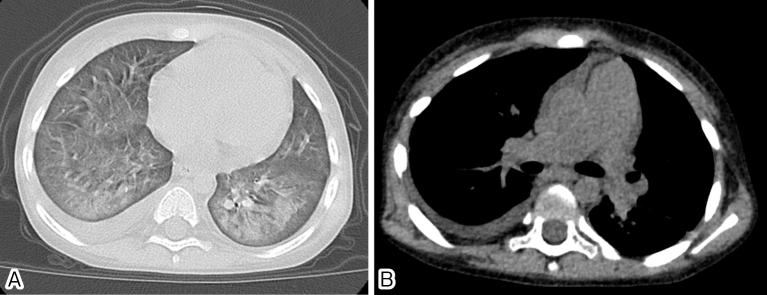

Case report: A 4-year-old boy was diagnosed with metastatic neuroblastoma and underwent intensive chemotherapy, autologous HSCT, and allogeneic cord blood transplantation (CBT). He experienced PVOD on day 194 following CBT after displaying upper respiratory symptoms and positive RSV antigen test results approximately one month prior. Pathological examination of a lung biopsy specimen revealed lung injury suspected to be associated with viral infection in addition to PVOD-related findings, suggesting that RSV infection might have contributed to the onset of PVOD.